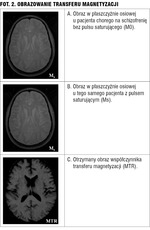

Co oczywiste, większa rozdzielczość przestrzenna poprawia skuteczność informatycznych algorytmów obliczeniowych w ocenie wolumetrycznej. W publikowanych analizach dowiedziono, że zmniejszenie grubości warstwy korowej jest najwyraźniejsze w płatach czołowych i skroniowych i wynosi u chorych na schizofrenię czy ADHD około 5-7 proc., a więc zmiany te są na tyle dyskretne, że przydatność pomiarów wolumetrycznych w codziennej praktyce jest ograniczona, choć pozwalają one na prawidłowe sklasyfikowanie zdrowych i chorych w 60-74 proc.[2] W schizofrenii stwierdzano również zmniejszenie objętości hipokampa i ciała migdałowatego oraz poszerzenie komór, zmniejszenie objętości podwzgórza i powiększenie jąder podstawy. Zmiany te owocują ogólnym zmniejszeniem objętości mózgu.[3,4] Także w depresji wieloepizodowej stwierdzono redukcję objętości hipokampa.[5] W jadłowstręcie z kolei obserwowano izolowane poszerzenie układu komorowego lub zmiany korowo-podkorowe jako wynik ogólnej redukcji masy mózgu, zwłaszcza kory mózgowej (pseudoatrofia podkorowa lub korowo-podkorowa).[6] Zaletą obrazowania metodą rezonansu magnetycznego poza obrazami morfologicznymi o wysokim kontraście tkankowym jest możliwość zastosowania dodatkowych technik pozwalających na wnioskowanie funkcjonalne. Jest to obrazowanie dyfuzyjne (DMR) i ocena transferu magnetyzacji, spektroskopia protonowa (1H MRS) i rezonans czynnościowy oparty o efekt BOLD (fMRI).